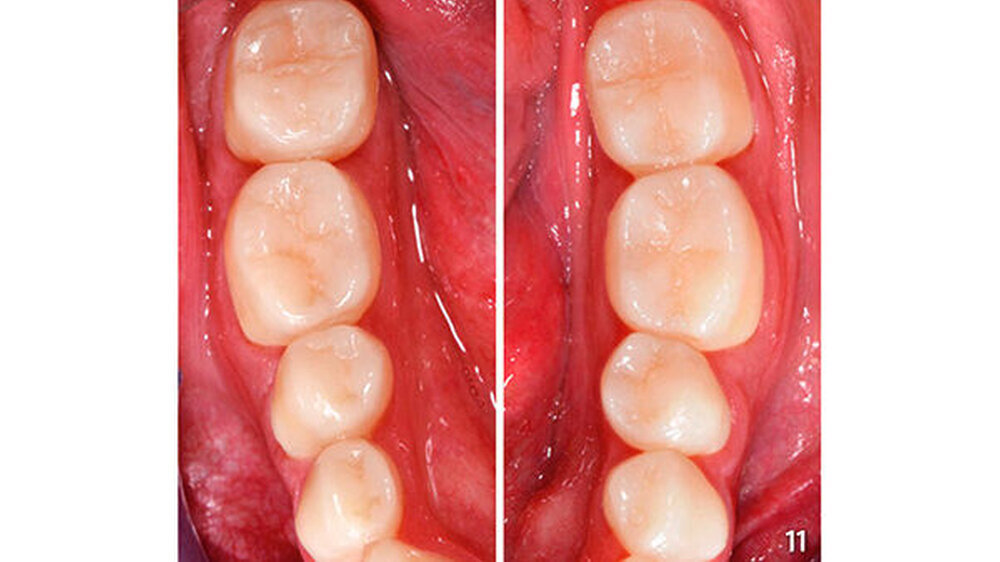

Die schwer zugänglichen Approximalflächen und -übergänge wurden mit oszillierenden, einseitig diamantierten Feilen (Proxo Shape Flexible, Fa. Intensiv, Grancia, Schweiz) ausgearbeitet und geglättet (Abb. 10). Mit dieser Technik wurden die Seitenzähne im Unterkiefer schrittweise aufgebaut und am Ende poliert (Abb. 11). Abschließend erfolgte die Versorgung der Frontzähne im Unterkiefer mit Komposit unter Verwendung der Bodymasse (Farbe A3B) des oben genannten Komposits (Abb. 12, 13).